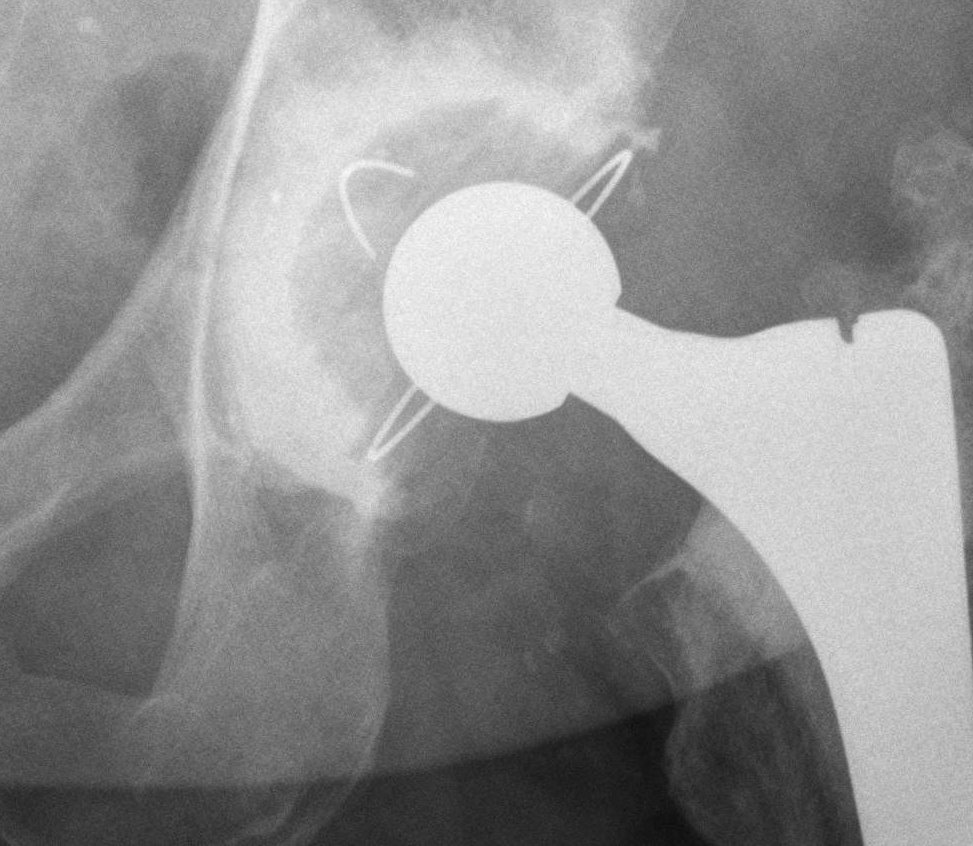

Inferior cement Inferior cement Intra-pelvic cement